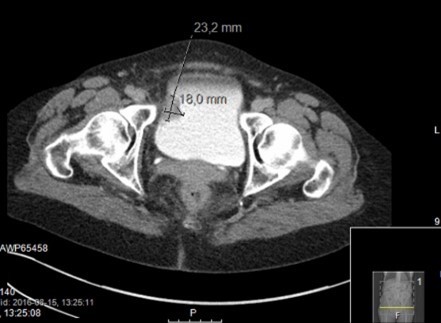

Förmodad urinblåsetumör

Vad ser du?

Vad är detta?

Cancer i urinblåsa (urotel)